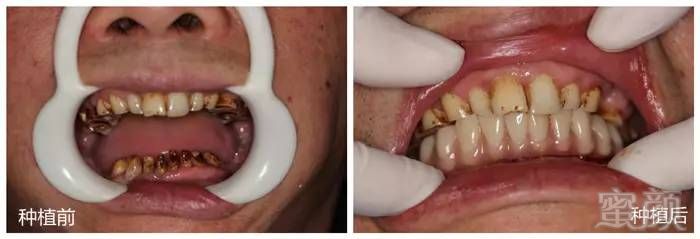

患者何先生,长期咀嚼槟榔,致下颌后牙全部缺失,下前牙全部松动。

带着还能嚼槟榔的心来到株洲市中心医院口腔科门诊种植中心咨询种牙。医生看到何先生蜡黄的牙齿,为他拍了个牙片:

发现其下前牙牙槽骨吸收严重,牙齿松动三度,无法保留,但这样一来,何先生下颌半口牙全部缺失,严重影响咀嚼和社交活动。

2017年5月26日,医生为何先生拔了那些松动的牙齿,并修整创缘,成固定角度对称植入种植体(那几个关键的钉子)。为了分散咬合力,每颗种植体的角度严格控制,这是“ALL- ON- 4”关键技术所在!

戴上临时义齿,可以满足患者对于美观和咀嚼的基本需要。戴上临时义齿后,何先生照着镜子欣赏着自己的牙齿,简直美翻了,没想到自己从开始手术到戴上假牙只用了短短5个小时,老婆再也不用当心他的吃饭问题了。

4.四~六个月后安装修复体

4~6个月后,种植体与牙槽骨完全结合牢固后,再安装上修复体。以后吃饭、社交、自拍那都不是事儿了,他人完全看不出这是一幅假牙。